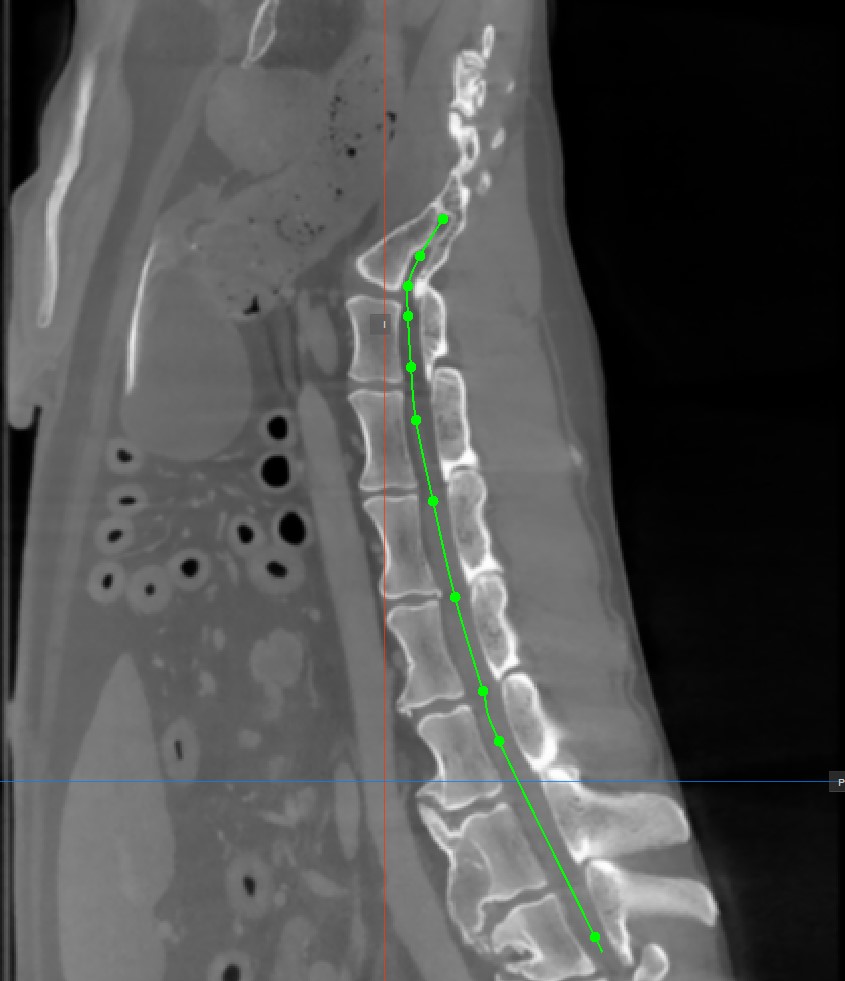

Az görbe befejezéséhez kattintson ismét az

Add CMPR Pointeszközre, vagy kattintson duplán a képre az utolsó pont elhelyezésekor. Az útvonal zöld színnel lesz megjelölve, miután véglegesítette.

A CMPR kiegyenesített nézete fölé helyezve a kurzort egy narancssárga pont jelenik meg az MPR képeken megrajzolt útvonalon, jelezve a kurzor pontos helyét.

Módosítsa a CMPR útvonalat a Elem kijelölése/mozgatása eszköz kiválasztásával, és rendelje hozzá az elérhető egérgombok egyikét. Nyomja le és húzza az útvonal egyik alap pontját a pozíció módosításához.